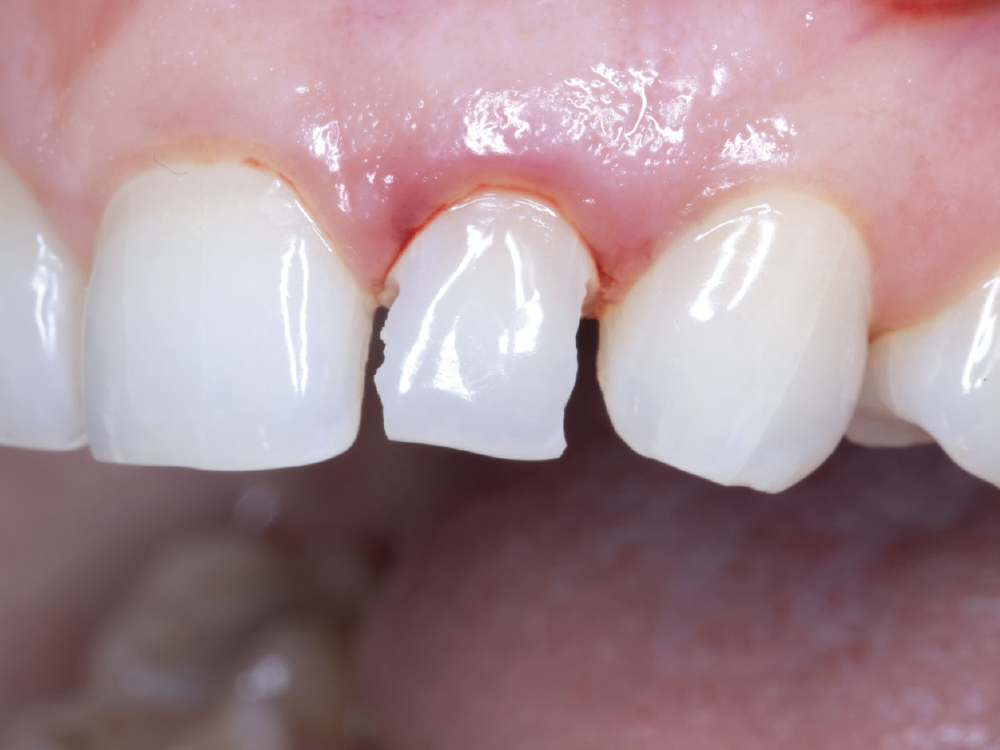

The emergence profile created by the custom healing abutment is crucial for maintaining the gingival architecture, ensuring proper alignment of the papilla, margins, and soft tissue. The healing abutment helps retain the patient’s natural tooth appearance as closely as possible throughout the healing process.

Figures 13a, 13b: The emergence profile created by the custom healing abutment is crucial for maintaining the gingival architecture, ensuring proper alignment of the papilla, margins, and soft tissue. The healing abutment helps retain the patient’s natural tooth appearance as closely as possible throughout the healing process.